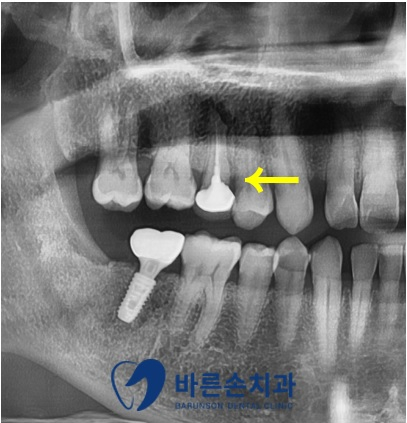

치아가 부러지기 전에 저희 치과에서 촬영한 엑스레이 자료가 있어

확인해 보니 이미 기존에 <신경치료와 포스트 크라운> 치료를 진행했던 치아라는 것을 알 수 있었습니다